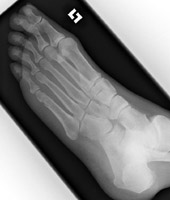

Metatarsal fractures are usually due to direct trauma. Often they are part of the Lisfranc fracture-dislocation spectrum.

- Click on the image for a larger versionAAP and oblique radiographs of the foot. These show a minimally comminuted fracture of the distal aspect of the second metatarsal.